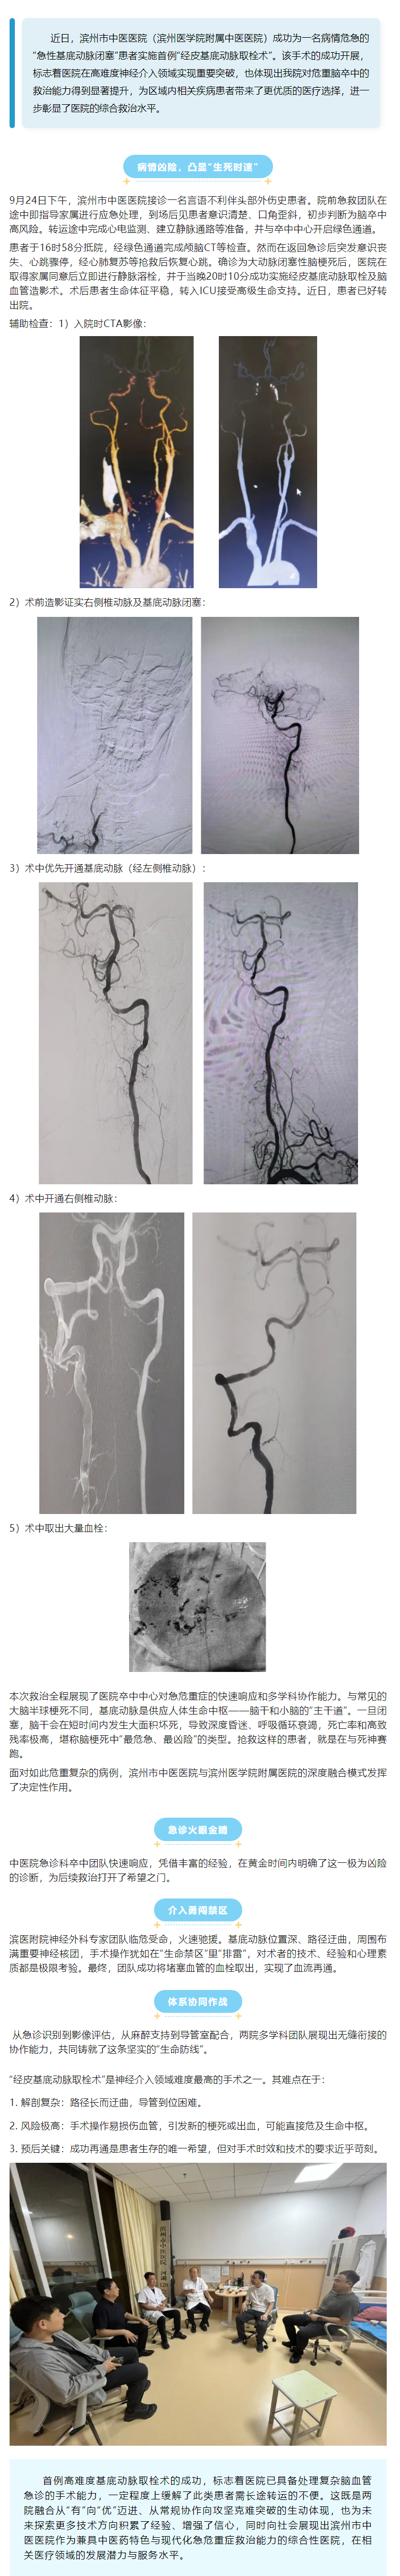

滨州市中医医院(滨州医学院附属中医医院)成功实施首例“经皮基底动脉取栓术”